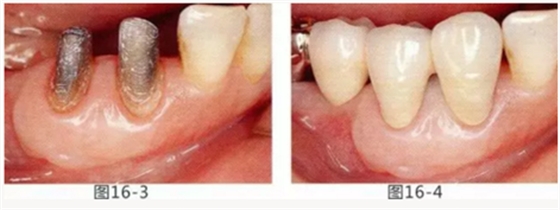

有3~4mm牙周袋并且沒(méi)有附著齦的存在,系帶也在牙頸部附近位置的病例。通過(guò)FGG(游離齦移植)獲得附著齦同時(shí)切除系帶后,即使經(jīng)過(guò)了很長(zhǎng)時(shí)間,牙齦邊緣依然保持安定的狀態(tài)。

圖16-1 右3,4牙周袋探診值為3~4mm,基本沒(méi)有附著齦。右下3部位的系帶也附著在牙頸部附近,由于清潔困難而引發(fā)了炎癥。

圖16-2 由于磨牙部缺失,為了能夠進(jìn)行固定修復(fù)而在右下6位置植入種植體,制作右下3,4,5,6固定橋冠。為了增加基牙右下3,4周圍的附著齦,在實(shí)施FGG同時(shí)去除系帶。

圖16-3 獲得了足夠附著齦,可以抵抗刷牙等外部刺激。

圖16-4 獲得充分附著齦,易清潔的狀態(tài)。修復(fù)體之間的鼓形間隙大小均一也使清潔性得到提升。